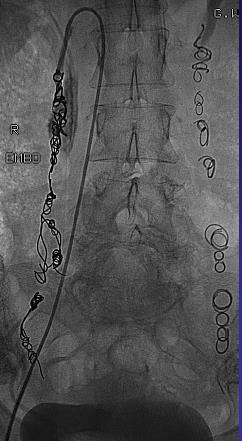

各种外科失败率,经阴囊低位显微外科精索静脉结扎术1.05%,精索静脉高位结扎术(high inguinal ligation)14.97%,外科整体失败率<5%。 内镜治疗: 近几年来,随着腹腔镜手术器械的进步和术者操作技能的提高,腹腔镜手术治疗精索静脉曲张日趋增多。 内镜治疗是有效的,但平均将近5小时的手术;几乎没有专门的外科医生用腹腔镜专此一项手术,需要几天住院且全麻,肾积水的危险。 经皮栓塞或硬化治疗 ![]() Gonadal Vein Embolization - Coils 双侧栓塞是安全和有效的。 1. 可以改善怀孕的可能性 2. 无需住院 3. 轻度疼痛 4. 肾积水的可能性低 5. 应用三明治技术(弹簧栓子-硬化剂-弹簧栓子)安全有效 6. 硬化剂或组织胶栓塞需要熟手 7. Onyx 比较贵和疼痛 8. 不管是外科或栓塞,不要忘了右侧精索静脉。 ![]() 1. Dubin L, Amelar RD. Varicocelectomy: 986 cases in a twelve-year study. Urology. 1977 Nov;10(5):446-9. 2. Morag B, Rubinstein ZJ, Madgar I, Lunnenfeld B. The role of spermatic venography after surgical high ligation of the left spermatic veins: diagnosis and percutaneous occlusion. Urol Radiol. 1985;7(1):32-4. 3. Zorgniotti AW, Sealfon AI. Scrotal hypothermia: new therapy for poor semen. Urology. 1984 May;23(5):439-41. 4. Marmar J. Male factor infertility: innovations in varicocele surgery. Nat Rev Urol. 2009 Sep;6(9):470-1. doi: 10.1038/nrurol.2009.143. 5. Kaufman SL, Kadir S, Barth KH, Smyth JW, Walsh PC, White RI Jr. Mechanisms of recurrent varicocele after balloon occlusion or surgical ligation of the internal spermatic vein. Radiology. 1983 May;147(2):435-40. |